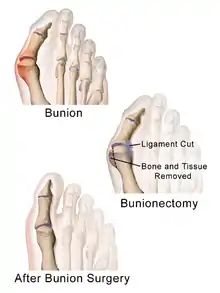

Surgery

Procedures are designed and chosen to correct a variety of pathologies that may be associated with the bunion. For instance, procedures may address some combination of:

- removing the abnormal bony enlargement of the first metatarsal,

- realigning the first metatarsal bone relative to the adjacent metatarsal bone,

- straightening the great toe relative to the first metatarsal and adjacent toes,

- realigning the cartilaginous surfaces of the great toe joint,

- addressing arthritic changes associated with the great toe joint,

- repositioning the sesamoid bones beneath the first metatarsal bone,

- shortening, lengthening, raising, or lowering the first metatarsal bone,

- correcting any abnormal bowing or misalignment within the great toe,

- connecting two parallel long bones side by side by syndesmosis procedure

At present there are many different bunion surgeries for different effects. The age, health, lifestyle and activity level of the patient may also play a role in the choice of procedure.

Traditional bunion surgery can be performed under local, spinal or general anesthetic. A person who has undergone bunion surgery can expect a 6- to 8-week recovery period during which crutches are usually required to aid mobility. An orthopedic cast is much less common today as newer, more stable procedures and better forms of fixation (stabilizing the bone with screws and other hardware) are used. Hardware may even include absorbable pins that perform their function and are then broken down by the body over the course of months. After recovery long term stiffness or limited range of motion may occur in some patients. Visible or limited scarring may also occur for patients.